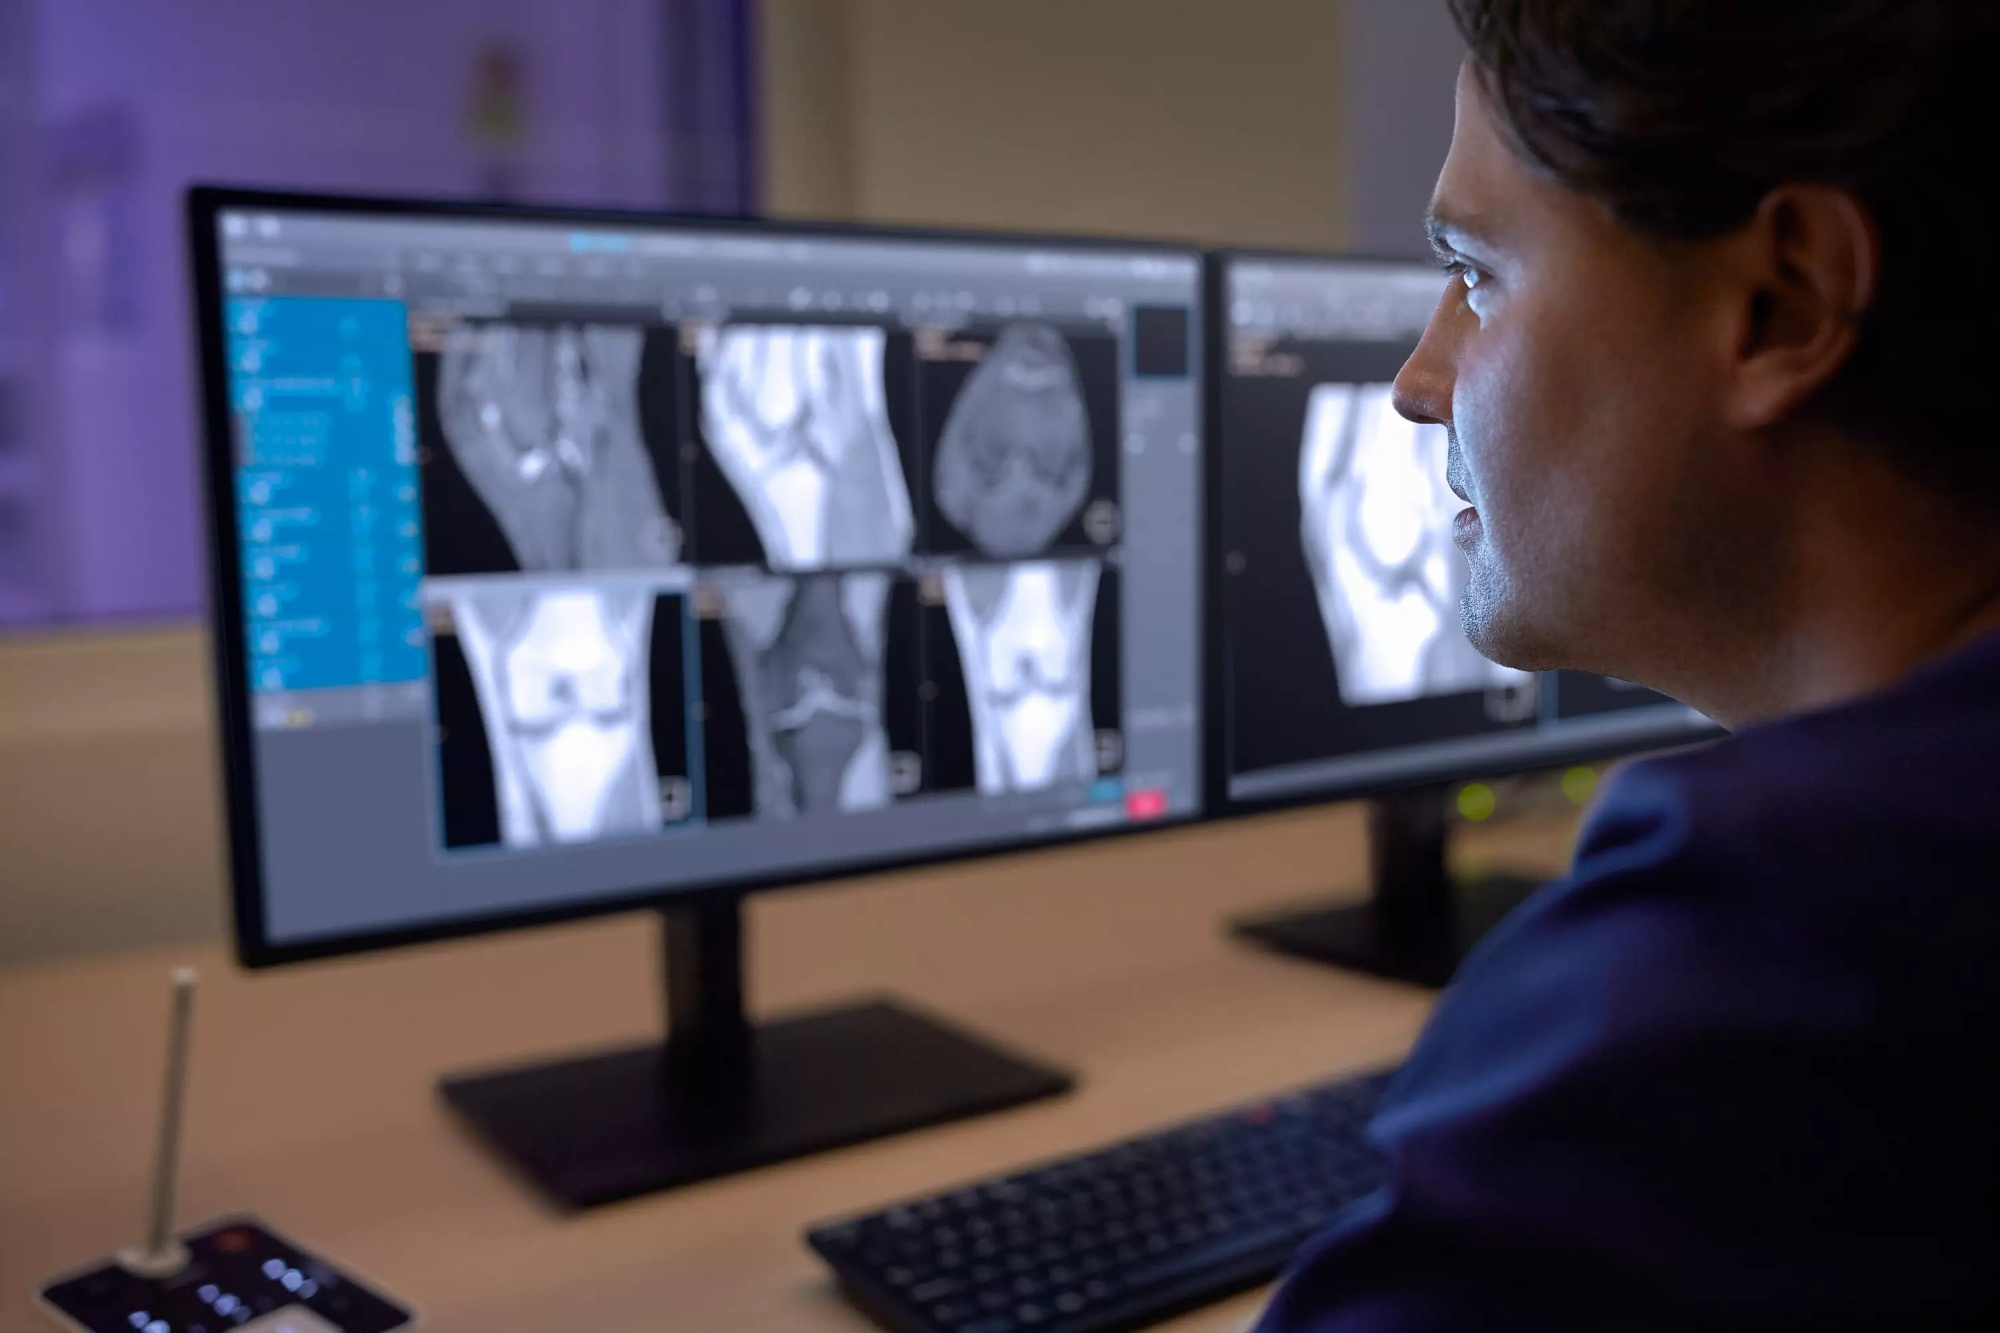

| Монитор рабочей станции | Консоль оператора с цветным монитором высокого разрешения (точная диагональ уточняется по ТЗ) |